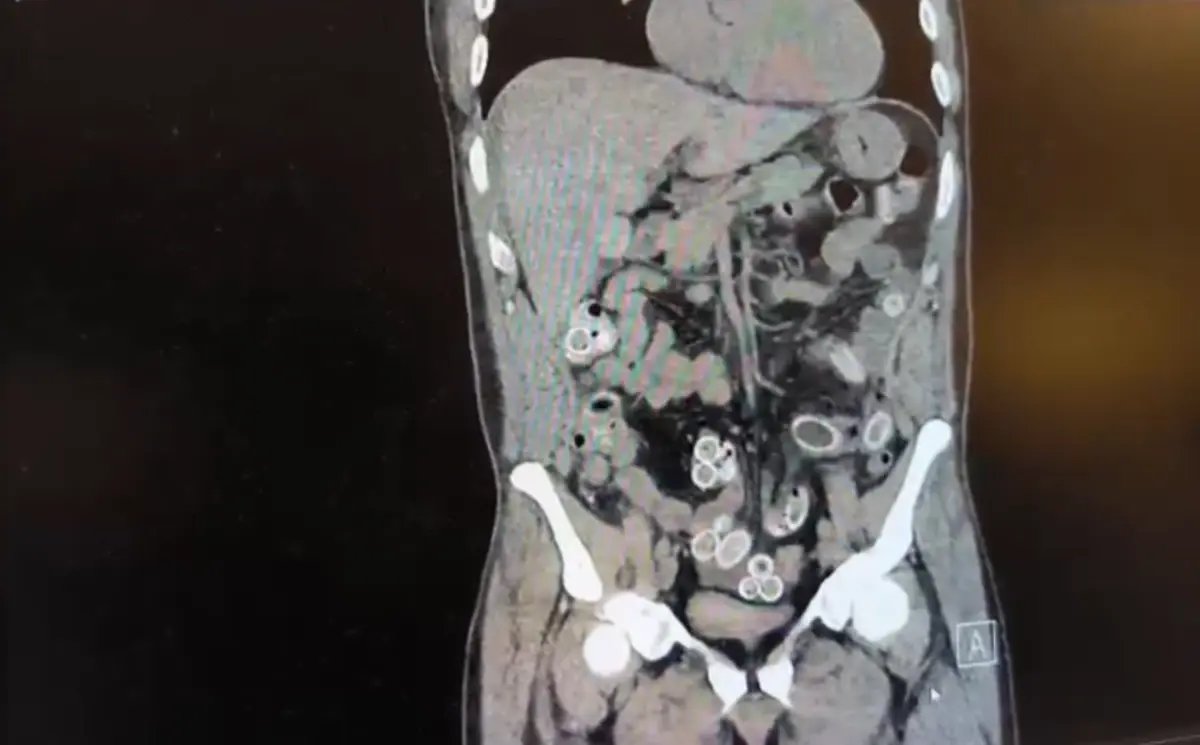

BEŞİKTAŞ'ta 3 bin kilometre uzaklıktaki Fas'tan uçakla Türkiye'ye gelen Cüneyt Ç. (52), 2 gün sonra mide ağrısı şikayetiyle hastaneye gitti. Tomografisi çekilen Cüneyt Ç.'nin mide ve bağırsaklarında yabancı madde bulunduğu tespit edildi. Hastane yetkililerinin bilgi vermesi üzerine Beşiktaş Asayiş Büro Amirliği ekipleri tarafından konuyla ilgili çalışma başlatıldı. Ameliyata alınan Cüneyt G.'nin mide ve bağırsaklarından kapsül halinde 49 adet esrar macunu çıkarıldı. Taburcu olmasının ardından gözaltına alınan Cüneyt G. tutuklandı.

Fas'tan yaklaşık 3 bin kilometre uzaklıktan uçakla Türkiye'ye gelen Cüneyt G., 2 gün sonra karın ağrısı şikayetiyle Fulya'daki özel bir hastaneye başvurdu. Yapılan muayenenin ardından Cüneyt G.'nin tomografisi çekildi. Şüphelinin mide ve bağırsaklarında yabancı madde tespit edilmesi üzerine hastane yetkilileri durumu polis ekiplerine bildirdi.

İhbar üzerine çalışma başlatan Beşiktaş Asayiş Büro Amirliği ekipleri, doktorlarla görüşme gerçekleştirdi. Doktorların değerlendirmesi sonrası ameliyata alınan Cüneyt Ç.'nin bağırsaklarından, toplam ağırlığı 259,7 gram olduğu öğrenilen 49 esrar macunu çıkarıldı. Şüpheliye ait 1 adet cep telefonu da hastane yetkilileri tarafından polis ekiplerine teslim edildi.